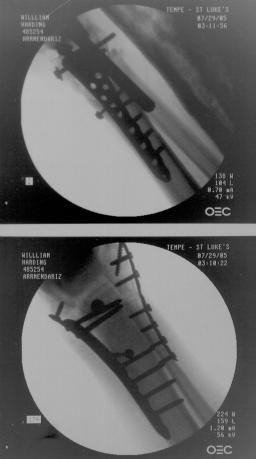

Screw Removed from Right Ankle

As can be noted in many of the right ankle x-rays, there was a screw that Dr. Keller placed in Liam’s lower right fibula which was

supposed to be through the plate in the fibula, but instead Dr. Keller missed the plate and simply screwed it into the bone. In the

position that the screw was place it caused considerable pain for Liam and obstructed Liam’s normal foot motion. The images below

show Dr. Gottlieb correcting Dr. Keller’s mistake.